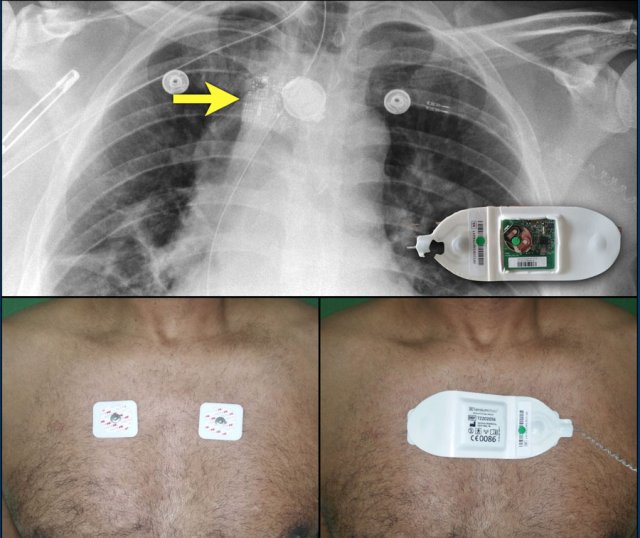

Subcutaneous ICD

The S-ICD or subcutaneous implantable cardioverter-defibrillator is not connected to the heart or the vessels.

A presternal wire is placed and connected to a laterally placed ICD with the heart located between the wire and the box.

This system is not capable of pacing the heart.

Loop recorders

Loop recorders are implantable cardiac monitors to continuously record the cardiac rhythm in patients with unexplained palpitations or syncope.

They are placed subcutaneously.

These devices are getting smaller and smaller and should not be mistaken for an USB flashdrive.

Loop recorders have a variety of uses including monitoring patients with unexplained syncopal episodes and assessment of patients with atrial fibrillation, ventricular arrhythmias, or conduction disturbances.

These recorders can provide more than a year of monitoring that may be activated by the patient or be automatically activated.

Another example of a loop recorder.